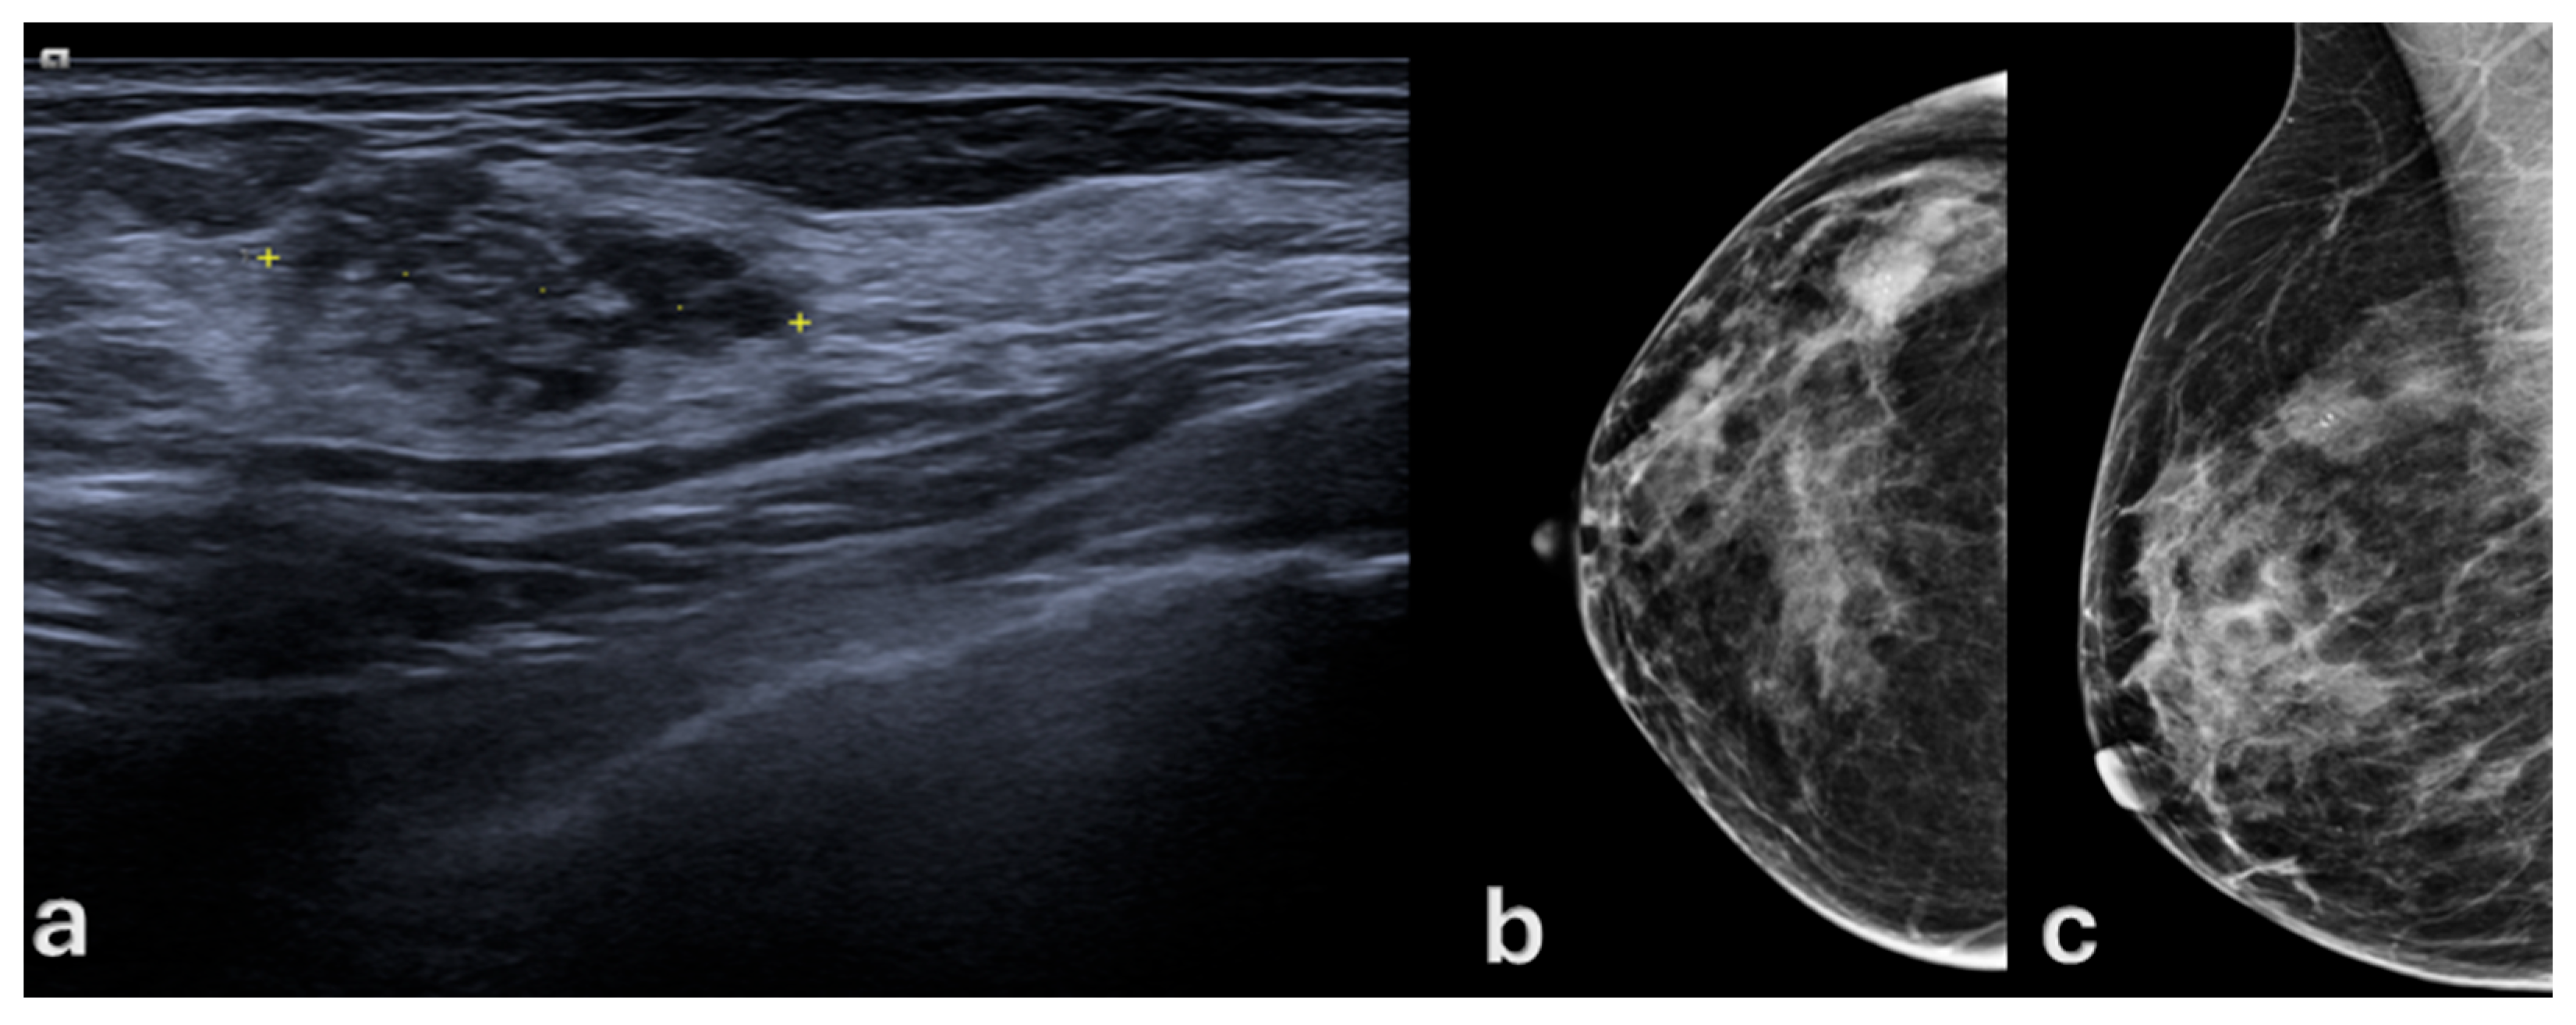

- Chiang, C.-L.; Liang, H.-L.; Chou, C.-P.; Huang, J.-S.; Yang, T.-L.; Chou, Y.-H.; Pan, H.-B. Easily recognizable sonographic patterns of ductal carcinoma in situ of the breast. J. Chin. Med. Assoc. 2016, 79, 493–499. [Google Scholar] [CrossRef][Green Version]

- Uematsu, T. Non-mass lesions on breast ultrasound: Why does not the ACR BI-RADS breast ultrasound lexicon add the terminology? J. Med. Ultrason. (2001) 2023, 50, 341–346. [Google Scholar] [CrossRef]

- Korpraphong, P.; Tritanon, O.; Tangcharoensathien, W.; Angsusinha, T.; Chuthapisith, S. Ultrasonographic characteristics of mammographically occult small breast cancer. J. Breast Cancer 2012, 15, 344–349. [Google Scholar] [CrossRef] [PubMed]